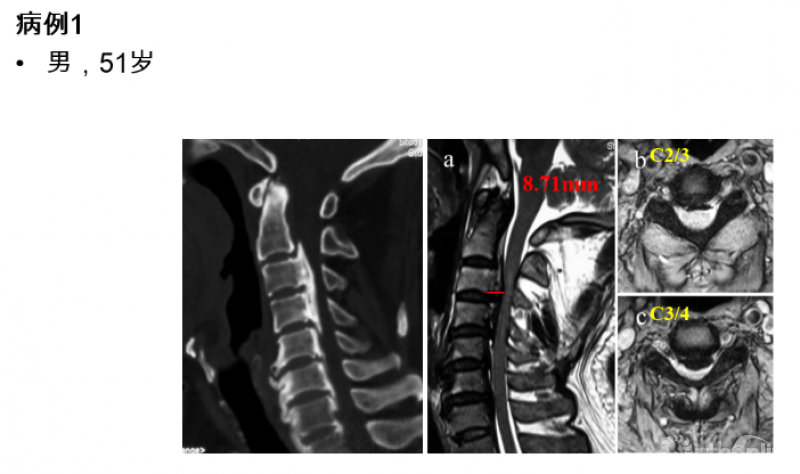

图1

从该患者的影像资料可以发现以下特点:致压物主要是来自于脊髓前方的后纵韧带骨化块,造成脊髓腹侧受压。在颈2/3间隙及以上水平,并未造成脊髓明显压迫,但在C3/4间隙水平椎管侵占率陡然增大,是脊髓受压最严重的节段。在这种情况下,颈后路纵向减压范围应该是C3-7、C2-7或者C1-7?

最后,我们回到病例一,利用上述研究结果指导临床决策:C3/4水平致压物中矢径8.71mm>7.1mm,所以C3-7减压势必残留压迫,应选择C2-7减压,术后获得了9.34mm的ACS,充分解除了脊髓压迫(图7)。

图7